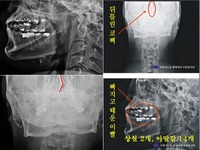

故 신해철 측 "경찰 수사발표, 대체로 인정"

警 "신해철 사망은 의료과실" 기소의견 檢 송치

신해철 사망, 결국 병원 측 의료과실 때문?가수 신해철이 병원 측 '의료 과실'로 사망한 것으로 보인다는 경찰 수사 결과가 나와 주목을 끌고 있다.서울 송파경찰서는 3일 "신해철 사망 직전 '장협착 수술'을 진행한 서울 S병원 K원장에게 업무상과실치사 혐의를 적용, 기